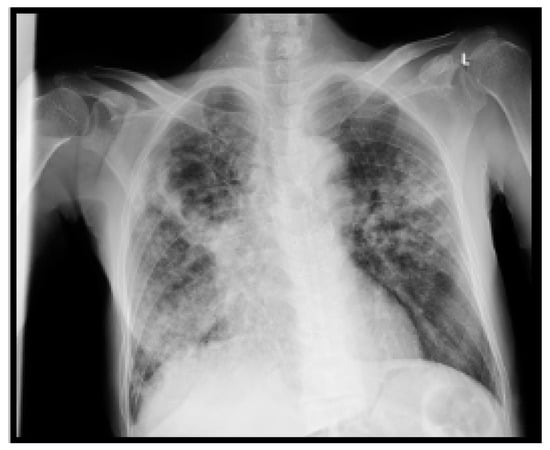

A summary of the patient’s CXR and lab investigations’ findings are demonstrated in Figure 4 and Table 4, respectively.

Figure 4. Posteroanterior chest X-ray (CXR) of the fourth case. The CXR shows diffuse reticular opacities are seen in both lungs with almost complete opacification of the left lung, which also shows faint cystic changes. Mild pneumothorax cannot be excluded with these cystic and emphysematous changes. The overall findings are suggestive of chronic interstitial lung disease (associated with cystic pattern), superimposed by consolidation in keeping with infection. Small bilateral pleural effusion is also seen.